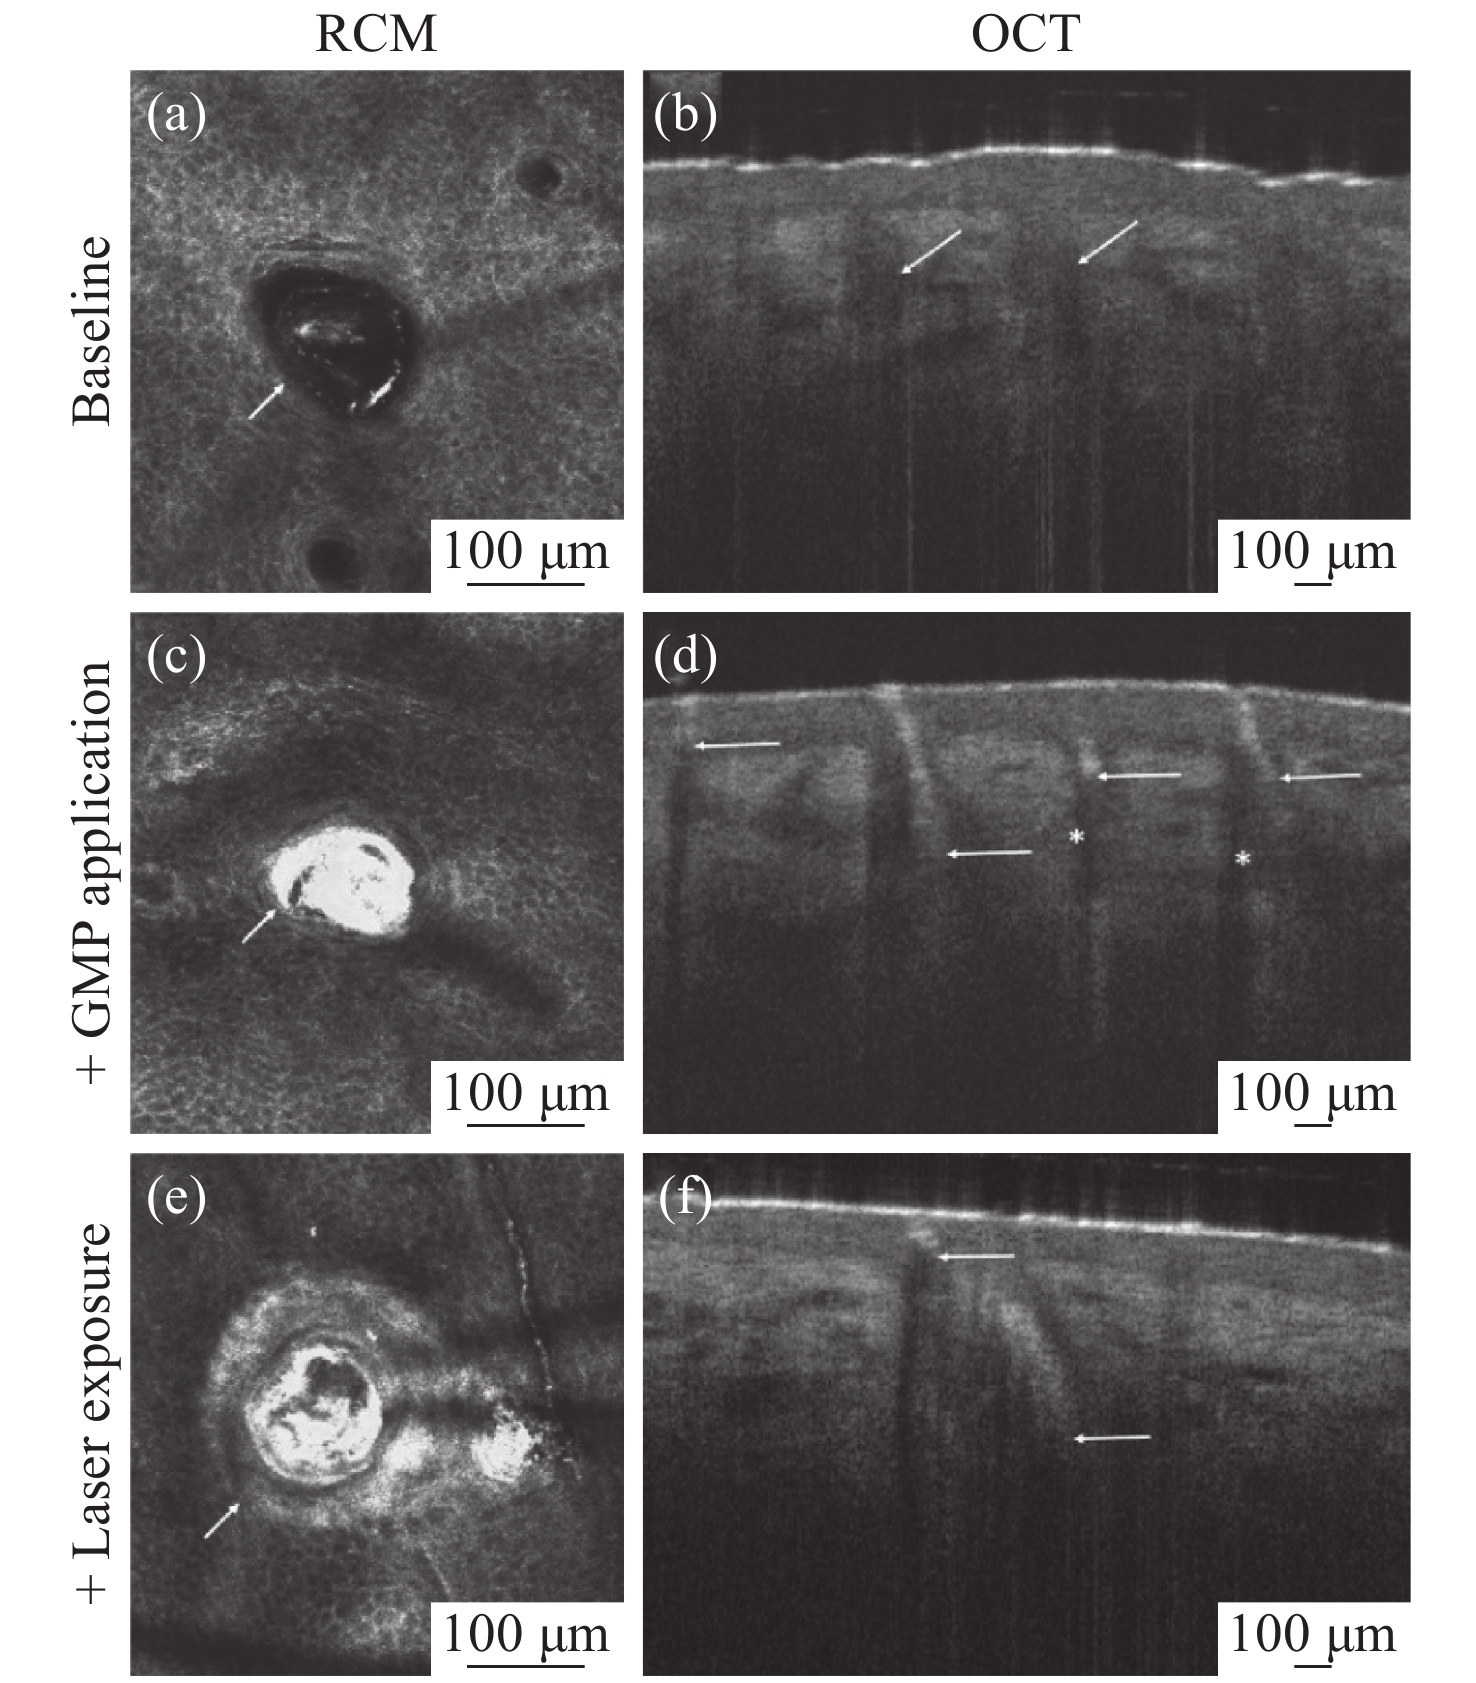

Optical Coherence Tomography (OCT) is a new imaging technique that uses interference in low coherent light by measuring the delay and magnitude of backscattered or reflected signals from the sample. OCT technology can provide real-time structural information with one-dimensional depth and two- and three-dimensional tomography at micron-scale resolution. Besides its high spatial resolution, OCT imaging is beneficial for its non-contact and non-invasive methodology. The system is also easy to operate and relatively portable. OCT technology is mainly applied in the biomedical imaging field for diagnoses, making up for the shortcomings of the low penetration depth in confocal microscopes and the low resolution in ultrasonic imaging. At present, OCT technology has been used as the clinical standard for the diagnosis of retinal diseases, and the combination of OCT technology and endoscope technology has become an important tool for the clinical diagnosis of cardiovascular and gastrointestinal diseases. It also provides references for early cancer diagnosis, surgical guidance and postoperative rehabilitation of musculoskeletal diseases. To broaden the application of OCT technology and improve its medical detection capabilities, researchers are committed to increasing the penetration depth of OCT imaging in biological tissue, improving the system's resolution and signal-to-noise ratio, and optimizing its overall performance. This review introduces the principle and classification of OCT systems, their applications and their recent progress in various biomedical fields.